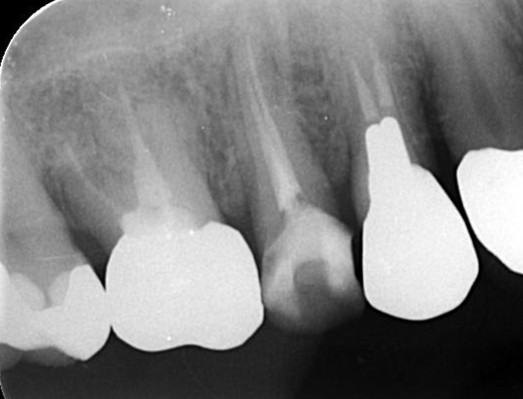

治療後 ![]() |

レントゲンで確認すると、ファイルが破折している可能性が確認できました。 |

精密検査の結果、折れた器具の見える位置にありますのでマイクロスコープを使い、自費診療の器具を用いれば除去できる可能性があります。 |